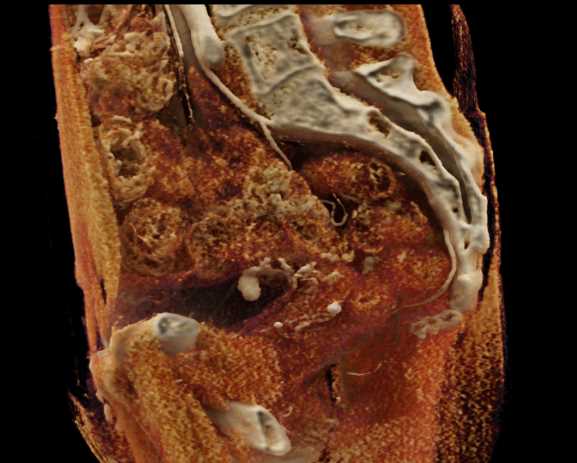

Urachal Carcinoma of the Bladder